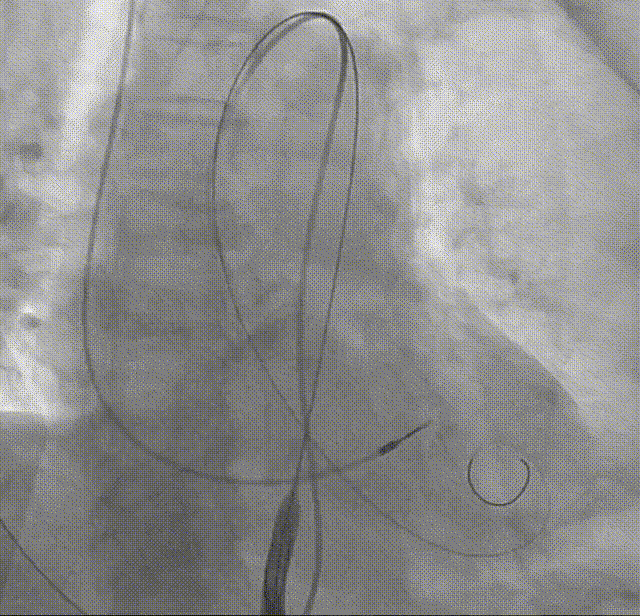

考虑瓣膜形态与位置均可,备球囊后扩处理方案,决定进行瓣膜脱钩,可见瓣膜脱钩稳定无位移

回收挂钩

22mm球囊后扩:可见瓣膜形态明显改善

造影评估:瓣膜形态与位置理想,瓣周漏明显减少,导管测量跨瓣压差12mmHg